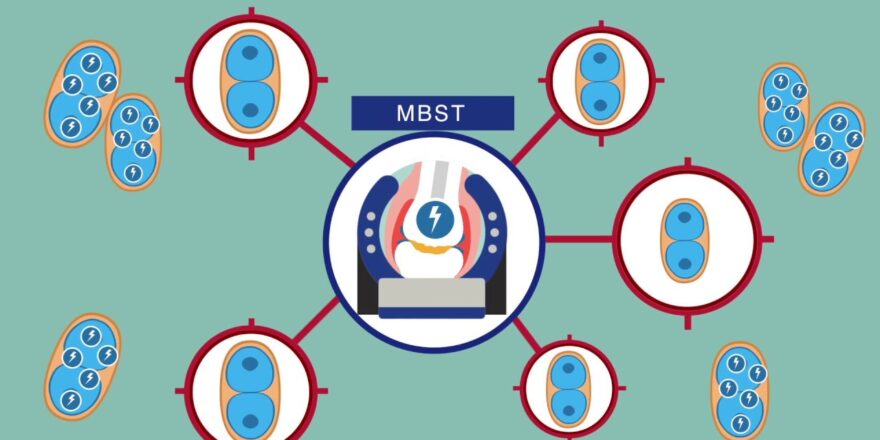

في مركز MBST للعلاج الفيزيائي وعلاج المفاصل في دبي، نقدم علاج MBST (العلاج بالرنين المغناطيسي) وهو علاج غير جراحي مصمم لتحسين صحة العمود الفقري، وتخفيف الألم، واستعادة القدرة على الحركة.

يستخدم علاج MBST مجالات كهرومغناطيسية منخفضة الطاقة لتحفيز تجديد الخلايا وإصلاحها داخل الأقراص الفقرية والعظام والأنسجة المحيطة. ويعمل على:

- تعزيز طاقة الخلايا: يزيد من إنتاج الـ ATP (طاقة الخلية) لتعزيز قدرة الخلايا على الإصلاح والتجديد.